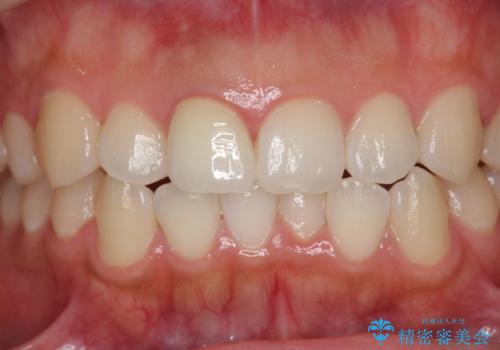

根管治療を行ったことで、歯ぐきのできものは治癒し再発をしなくなりました。

歯ぐきにできものができた 前歯の色調改善